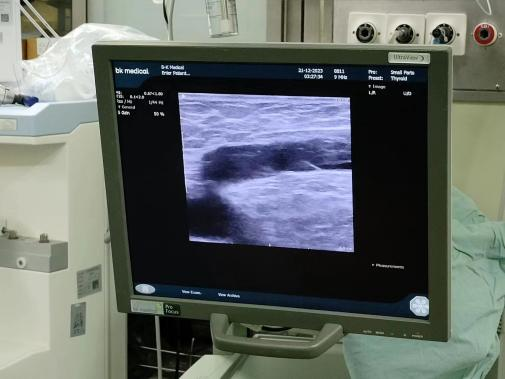

• 步骤2:B超引导下穿刺大隐静脉(膝关节附近),放置射频导管距离隐股交界2cm。

图片

• 步骤3:B超引导下由下至上注射肿胀液。肿胀液可以抵消热能对周围组织的损害;压迫静脉腔,排空血液;增加了静脉壁的粘附,产生更多的消融作用。